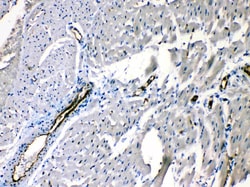

Reconstitute with 0.2 mL of distilled water to yield a concentration of 500 μg/mL. Positive Control - WB: rat stomach tissue, mouse ovary tissue. IHC: mouse intestine tissue, rat intestine tissue, rat cardiac muscle tissue, human intetsinal cancer tissue.

| Immunohistochemistry (Paraffin), Western Blot | |